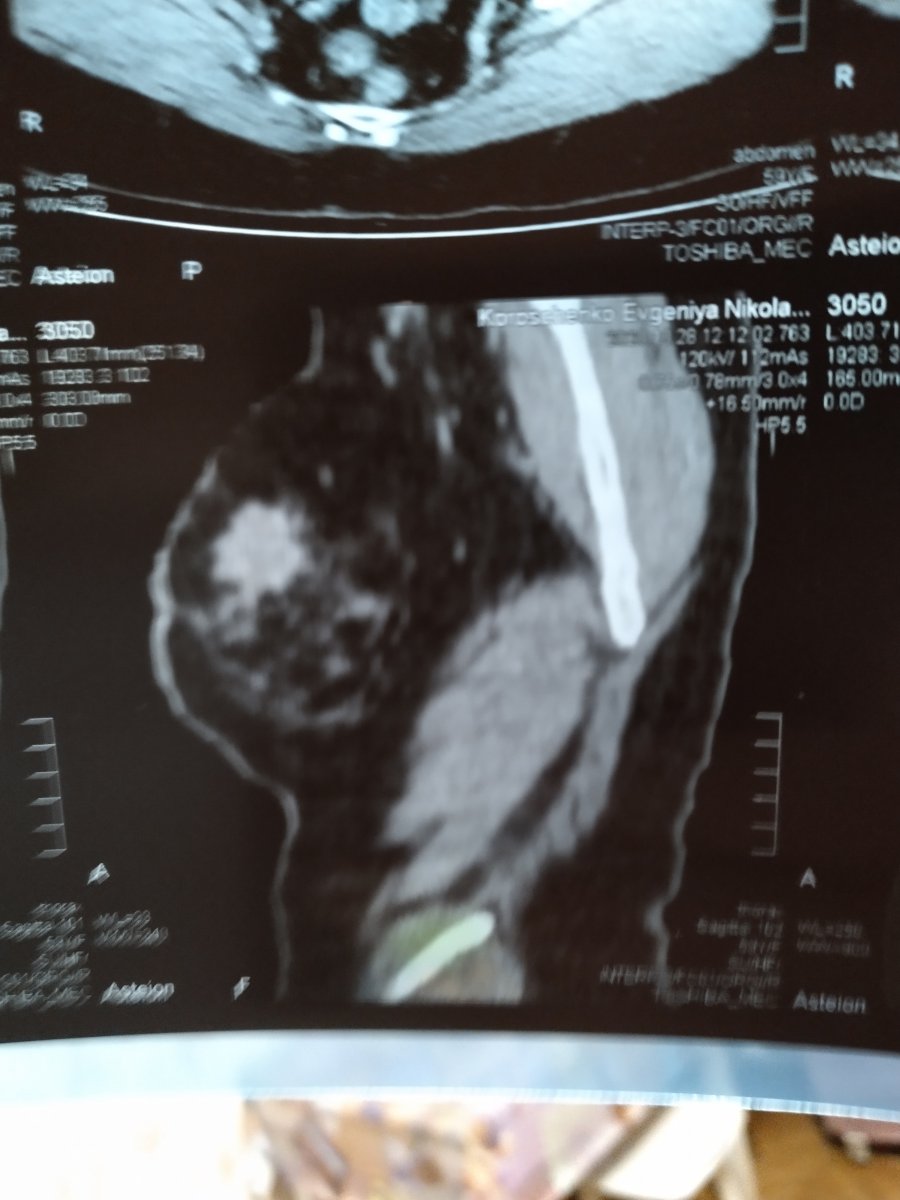

Комради прошу вашої допомоги, вже більше тижня як ми узнали страшну новину, в моєї мами пухлина в груді, зараз пройшли обстеження , з результатів КТ видно що треба операція та подальше лікування, на щастя в неї ще нічого не болить і врятувати її можна. Знайшли гарного лікаря Мотузяк Ігор Миколайович, чекаємо на результати біопсії та зразу ляжемо на операцію. Я Працюю в Києві кошти збираємо ,але боюсь що їх не вистачить в кого є можливість будь ласака допоможіть карта приват 4149609003427152 Корощенко Евгений Иванович

Маму я забрал в Киев, будем лечить в национальном институте рака нашол хорошего врача, вас я прошу о материальной помощи, если есть такая возможность извините заранее что беспокою , но ради жизни и здоровья мамы я готов на всё, стучюсь везде, где только можно. Белое неровное пятно на снимке это и есть та зараза которая угрожает её жизни , стадия ещё пока 2 но данное новообразование очень агрессивно и важно начать лечение уже сейчас. Одним нам не справиться пожалуйста помогите, может кому что надо из моих лотов продам с хорошей скидкой.

За любую помощь буду благодарен до конца жизни моя карта приват 4149609003427152 Корощенко Евгений Иванович